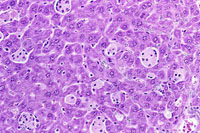

Kupffer cell hyperplasia and hypertrophy is rarely seen in mice. Hypertrophic Kupffer cells may contain pigment in some cases.

Examples of Kupffer cell hyperplasia.